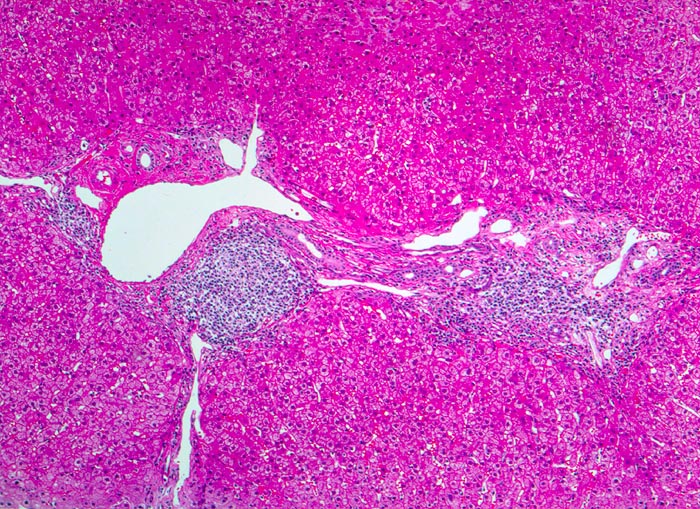

chronische Hepatitis C mit geringgradiger Aktivität und Fibrose

Dichtes lymphoides Infiltrat in den Portalfeldern mit Ausbildung eines Follikels. Stellenweise greift die Entzündung auf das angrenzende Parenchym über ( periportale Hepatitis). Zwischen den fibrosierten Portalfeldern verlaufen bindegewebige Septen.

Die Ausbildung von Lymphozytenaggregaten in Form von Follikeln in den Portalfeldern ist typisch aber nicht pathognomonisch für die chronische Hepatitis C.

Intravenöser Drogenabusus vor 10 Jahren. Damals Infektion mit dem Hepatitis C Virus.